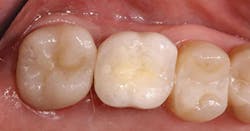

An e.max crown was created on tooth No. 15 (Fig. 7). As evident in the postoperative photo and bitewing (Figs. 8 and 9), there has been a significant improvement in the esthetics, form, and fit as compared to the original crown.